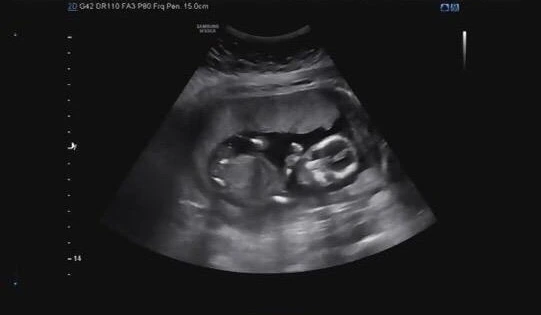

임신 12주 차, 아기 다운 모습이 보이는 "봉주"